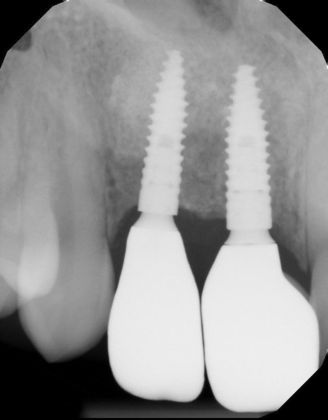

Two implants with crowns replacing infected root canals and old porcelain fused to metal crowns